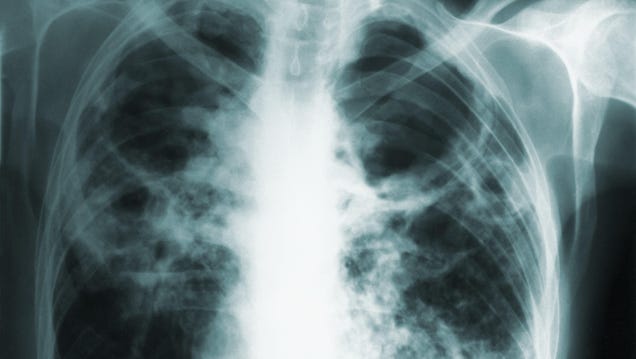

A woman’s active case of tuberculosis has prompted health officials in Washington state to alert the public. The woman has reportedly turned down treatment for over a year and disobeyed multiple court orders to stay isolated from others. The health department may pursue further legal action against the woman should…

Source: Gizmodo – A Washington Woman Could Land in Jail After Refusing Tuberculosis Treatment